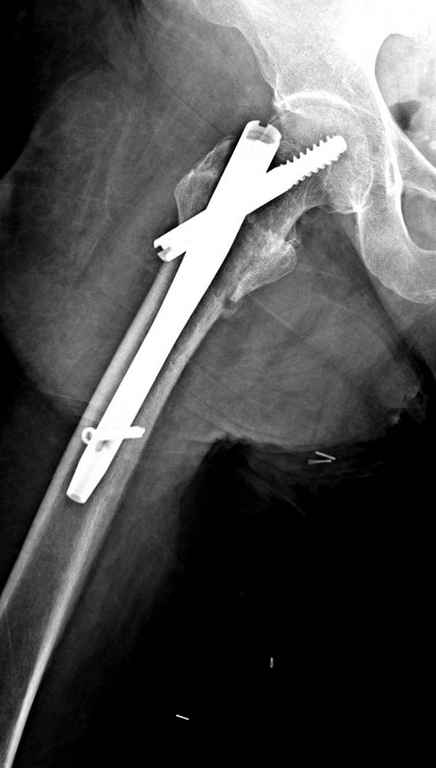

Перелом тут больше подвертельный. Нагрузка без торцевого упора на уровне перелома привела к телескопированию отломков на стержне. Ну и варус небольшой тоже свою лепту внес - если бы его не было, контактирующие латеральные стенки обоих отломков предотвратили бы укорочение, да и срослось бы за пару месяцев. А раз не срослось, упора отломков нет, более слабым местом оказались не нижние винты, а кость в головке и шейке. Так что надо было хотя бы удалить нижние винты до начала полной нагрузки.

Наверно, эндопротезирование. Есть более щадящий вариант - реостеосинтез (с устранением варуса и укорочения!), а после сращения и при наличии выраженного болевого синдрома - стандартное протезирование.

В данном случае в головке бедра и в вертлужной впадине огромный дефект, навряд ли удалением импланта или заменой на другой можно сохранить сустав.

Вашему вниманию представляется похожий случай, пациентке 70, осложнился в течение одного месяца после операции. Ревизия с заменой сустава, кабельная фиксация на трохантер. При установке в дистальном диафизе обнаружен тонкий кортикальный слой и сделана профилактика от возможного перелома аллографтом.